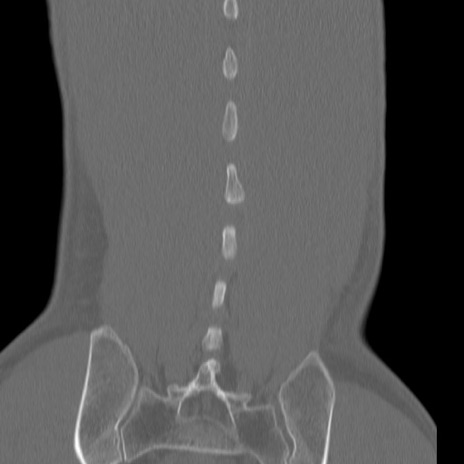

症例3 腰椎CT(冠状断像)

腰椎CT

3D再構成